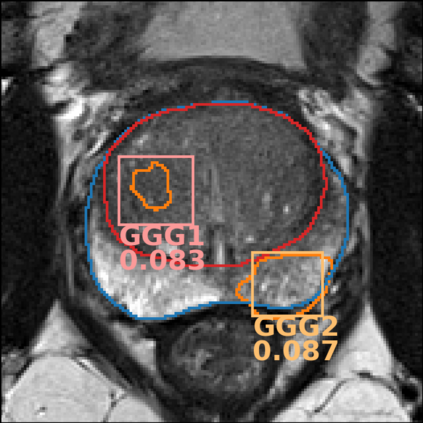

The emergence of multi-parametric magnetic resonance imaging (mpMRI) has had a profound impact on the diagnosis of prostate cancers (PCa), which is the most prevalent malignancy in males in the western world, enabling a better selection of patients for confirmation biopsy. However, analyzing these images is complex even for experts, hence opening an opportunity for computer-aided diagnosis systems to seize. This paper proposes a fully automatic system based on Deep Learning that takes a prostate mpMRI from a PCa-suspect patient and, by leveraging the Retina U-Net detection framework, locates PCa lesions, segments them, and predicts their most likely Gleason grade group (GGG). It uses 490 mpMRIs for training/validation, and 75 patients for testing from two different datasets: ProstateX and IVO (Valencia Oncology Institute Foundation). In the test set, it achieves an excellent lesion-level AUC/sensitivity/specificity for the GGG$\geq$2 significance criterion of 0.96/1.00/0.79 for the ProstateX dataset, and 0.95/1.00/0.80 for the IVO dataset. Evaluated at a patient level, the results are 0.87/1.00/0.375 in ProstateX, and 0.91/1.00/0.762 in IVO. Furthermore, on the online ProstateX grand challenge, the model obtained an AUC of 0.85 (0.87 when trained only on the ProstateX data, tying up with the original winner of the challenge). For expert comparison, IVO radiologist's PI-RADS 4 sensitivity/specificity were 0.88/0.56 at a lesion level, and 0.85/0.58 at a patient level. Additional subsystems for automatic prostate zonal segmentation and mpMRI non-rigid sequence registration were also employed to produce the final fully automated system. The code for the ProstateX-trained system has been made openly available at https://github.com/OscarPellicer/prostate_lesion_detection. We hope that this will represent a landmark for future research to use, compare and improve upon.